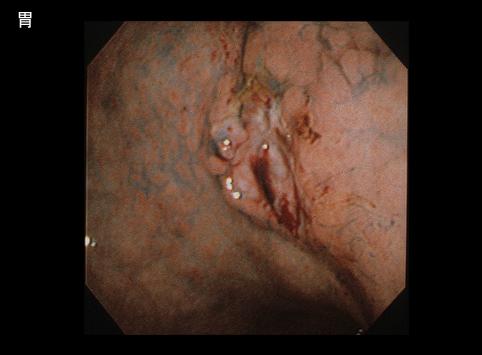

위, 십이지장, 대장에 다발병변을 보인 MLP형 악성 림프종

[Image-ID:7133]

악성 림프계종양/MLP형 악성 림프종

위(부위)/체부

내시경

15~19